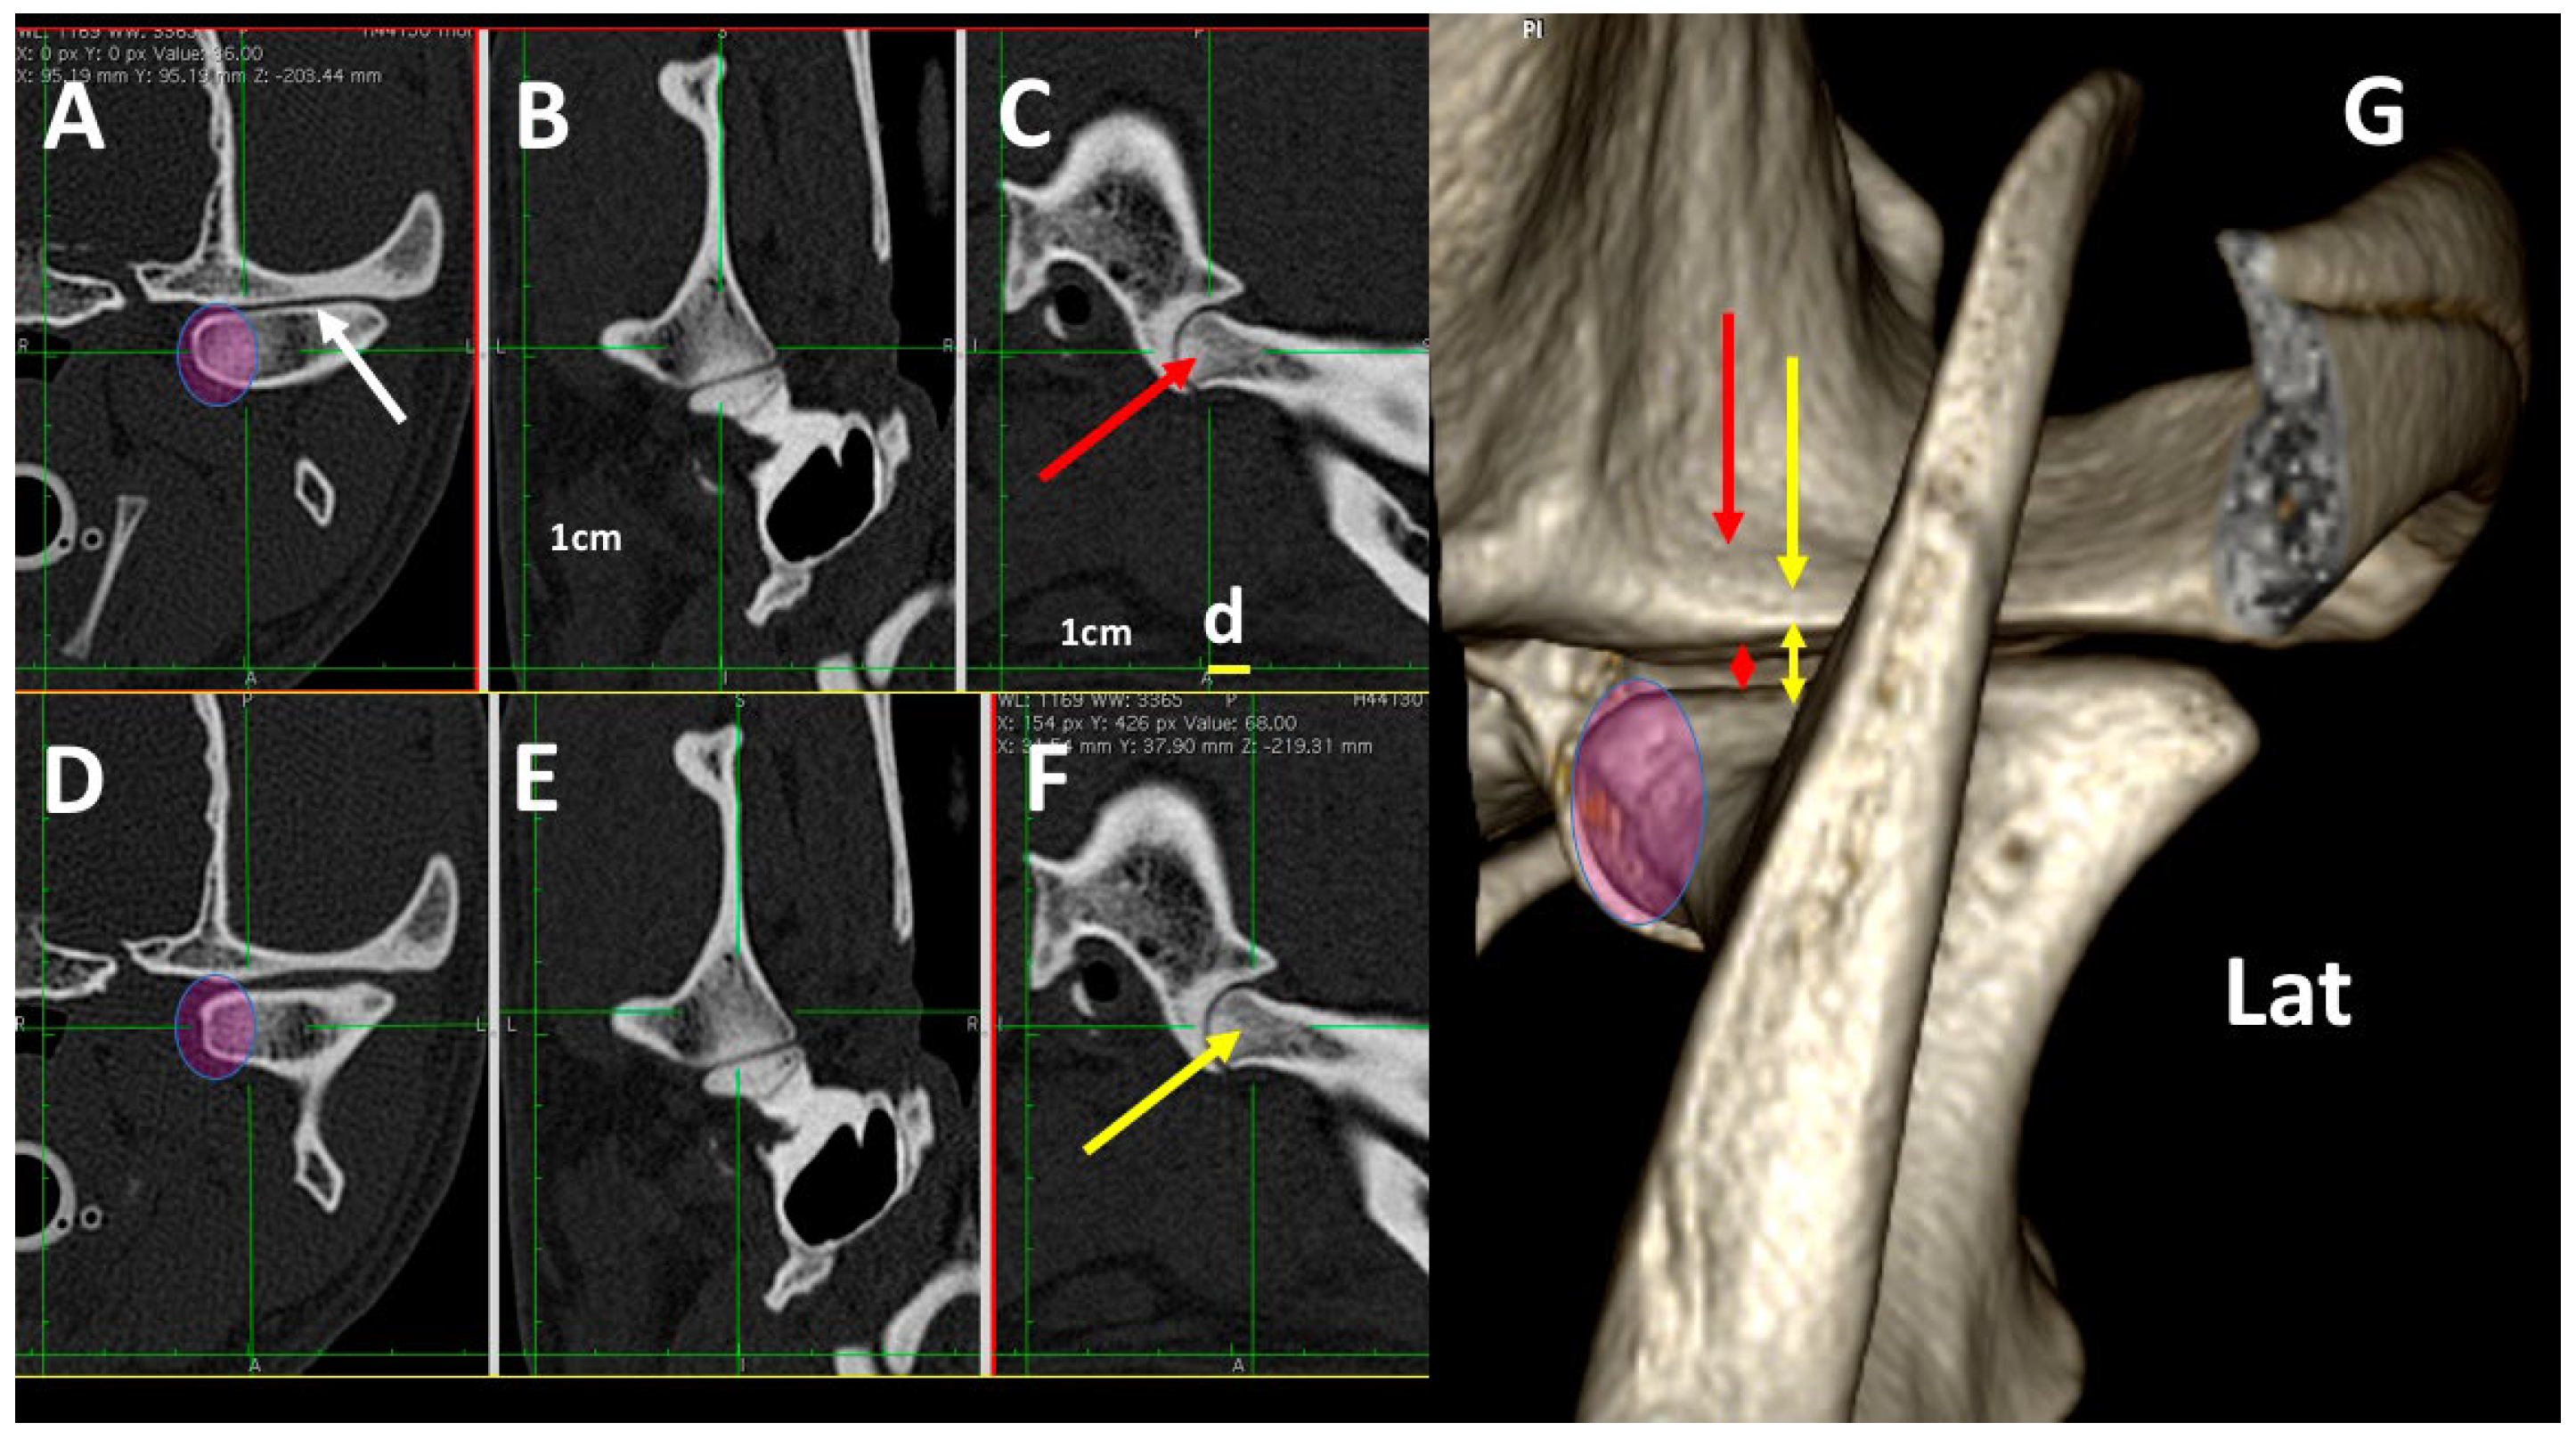

3.3. A Detailed Assessment of Each TMJ Comparing 3DVR Images with the Three Standard CT Planes